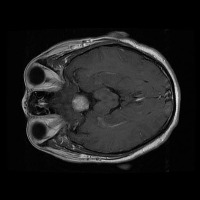

Early Detection of Brain Tumors: Use the "tesis" model to analyze MRI scans of patients proactively during routine check-ups, helping in the early identification of the presence of lesion selar or tumor hipofisario, leading to timely and potentially life-saving interventions.

Assisting in Treatment Planning: Oncologists and neurosurgeons can use the "tesis" model to study the location, size, and class of a patient's tumor. This helps in determining the best treatment options and surgical approaches, ultimately improving patient outcomes.

Medical Education and Training: Incorporate the "tesis" model in medical school curricula and professional trainings aimed at educating future doctors and radiologists about the identification and treatment of lesion selar and tumor hipofisario.

Research Tool for Cancer Studies: The "tesis" model can serve as a tool for researchers working on experimental treatments or clinical trials focused on lesion selar and tumor hipofisario. By identifying tumor classes efficiently and consistently, the model can help researchers compare treatment efficacy and study tumor progression over time.

Second Opinion Provider: Medical professionals can use the "tesis" model to double-check their own findings when analyzing brain MRI scans. This can reduce the likelihood of diagnostic errors and help confirm the presence of lesion selar or tumor hipofisario, resulting in more accurate decision-making.